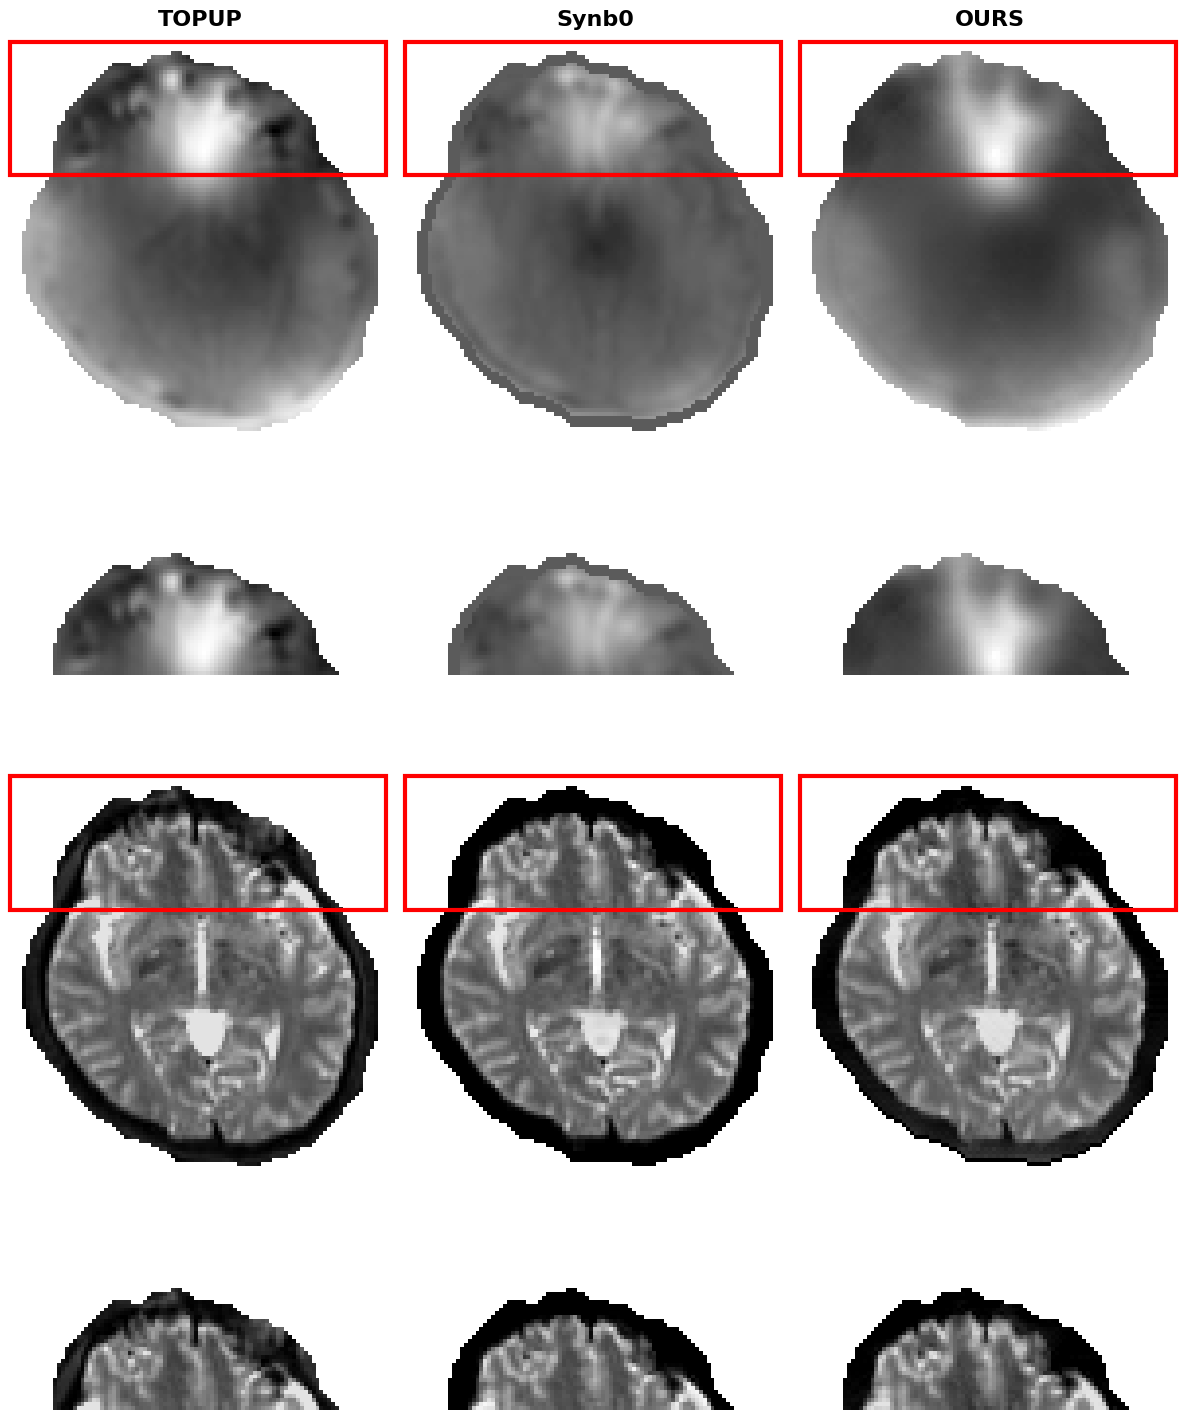

Figure 2 showcases the results of the proposed method, including the predicted VDMs and corrected b0 images, compared to those generated by and Synb0. While typically achieves the best anatomical alignment, thanks to its use of both blip-up and blip-down acquisitions, it cannot be applied when only a single phase-encoded image is available. Synb0 often under or overestimates broad distortion patterns. By contrast, our network learns a more accurate displacement map from a single input image. These results suggest that our approach can deliver near– quality with a single input image, making it a versatile alternative in data-limited scenarios.